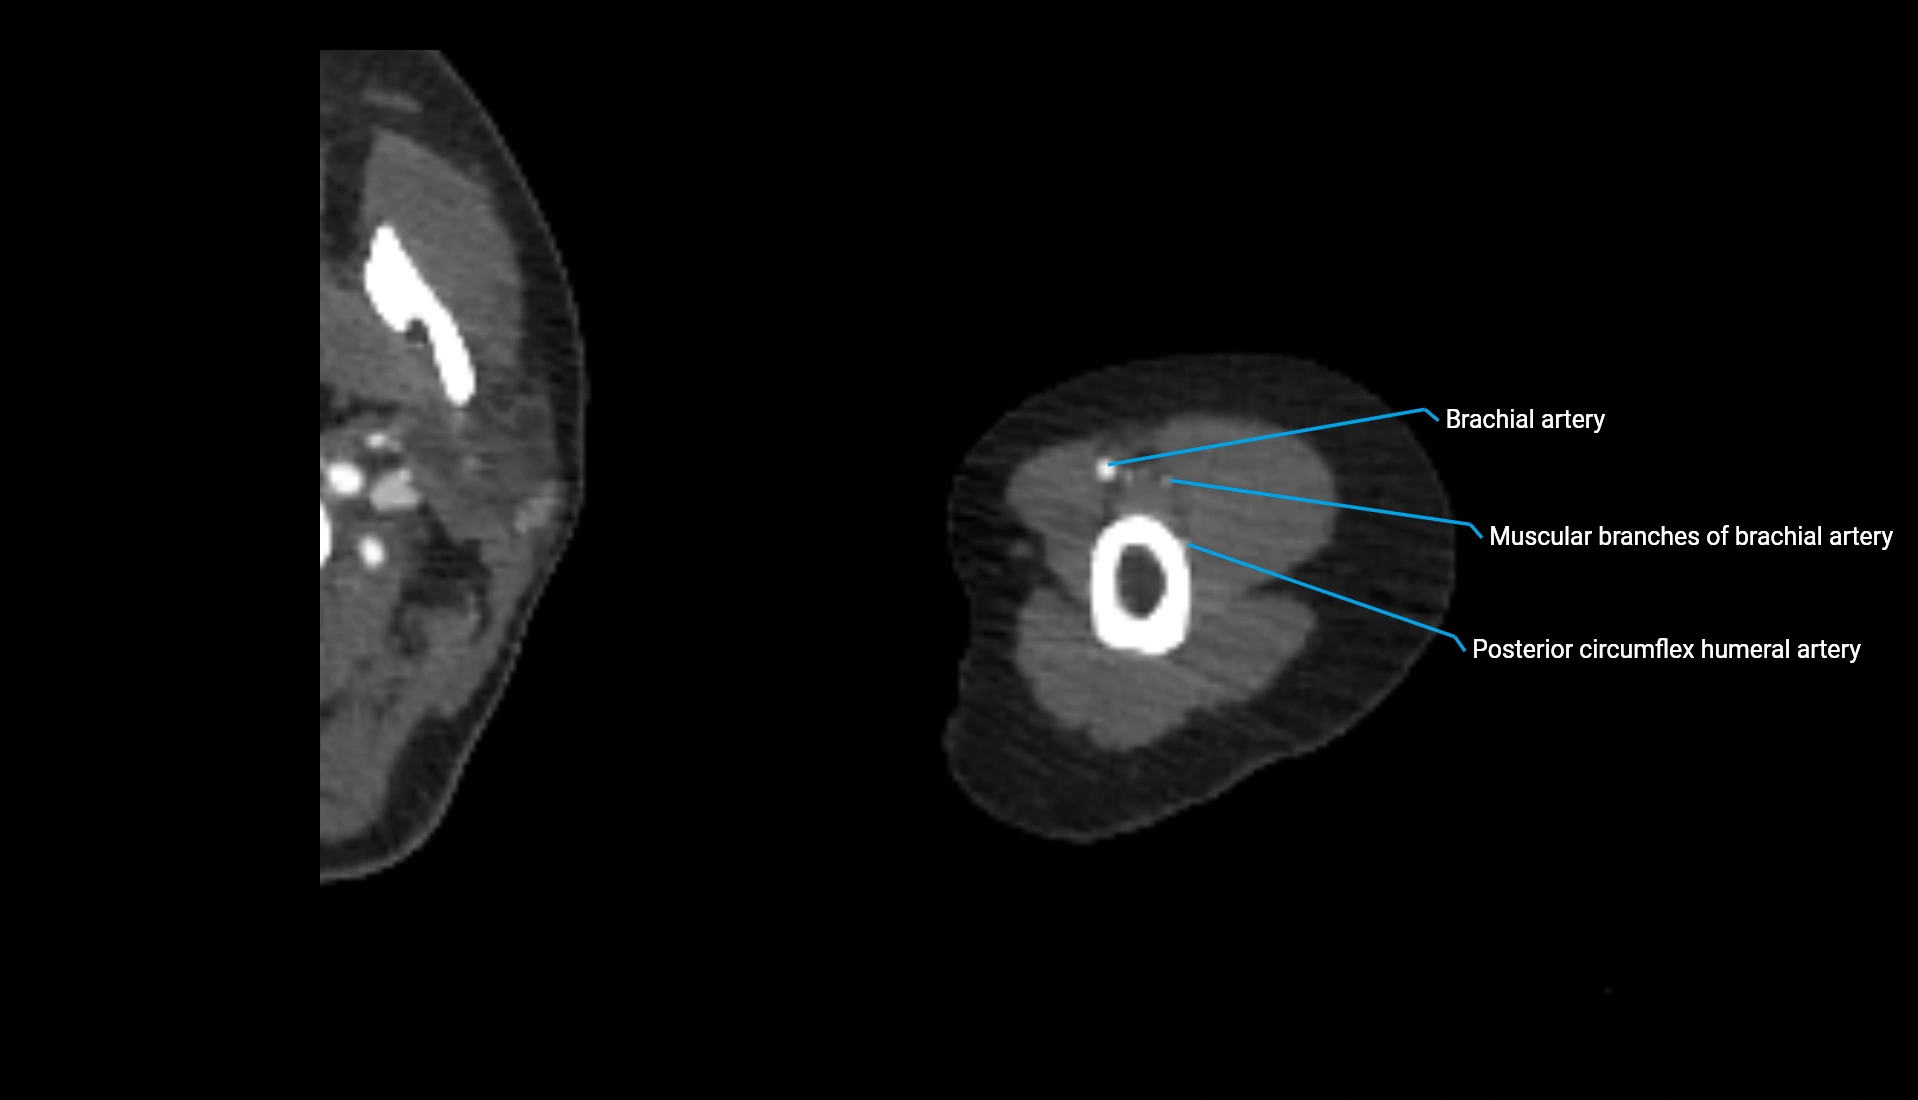

CT Appearance

Non-Contrast CT:

• Cortex: High-density, sharply defined

• Subchondral bone: Dense cancellous matrix

• Articular surface: Smooth concave contour articulating with the capitellum

• Excellent for evaluating bone integrity, alignment, and subtle fractures

Post-Contrast CT:

• Bone: No enhancement

• Joint capsule and synovium: Mild enhancement outlining the joint

• Improves contrast between soft tissues and bony margins

• Useful in detecting subtle joint abnormalities or postoperative changes